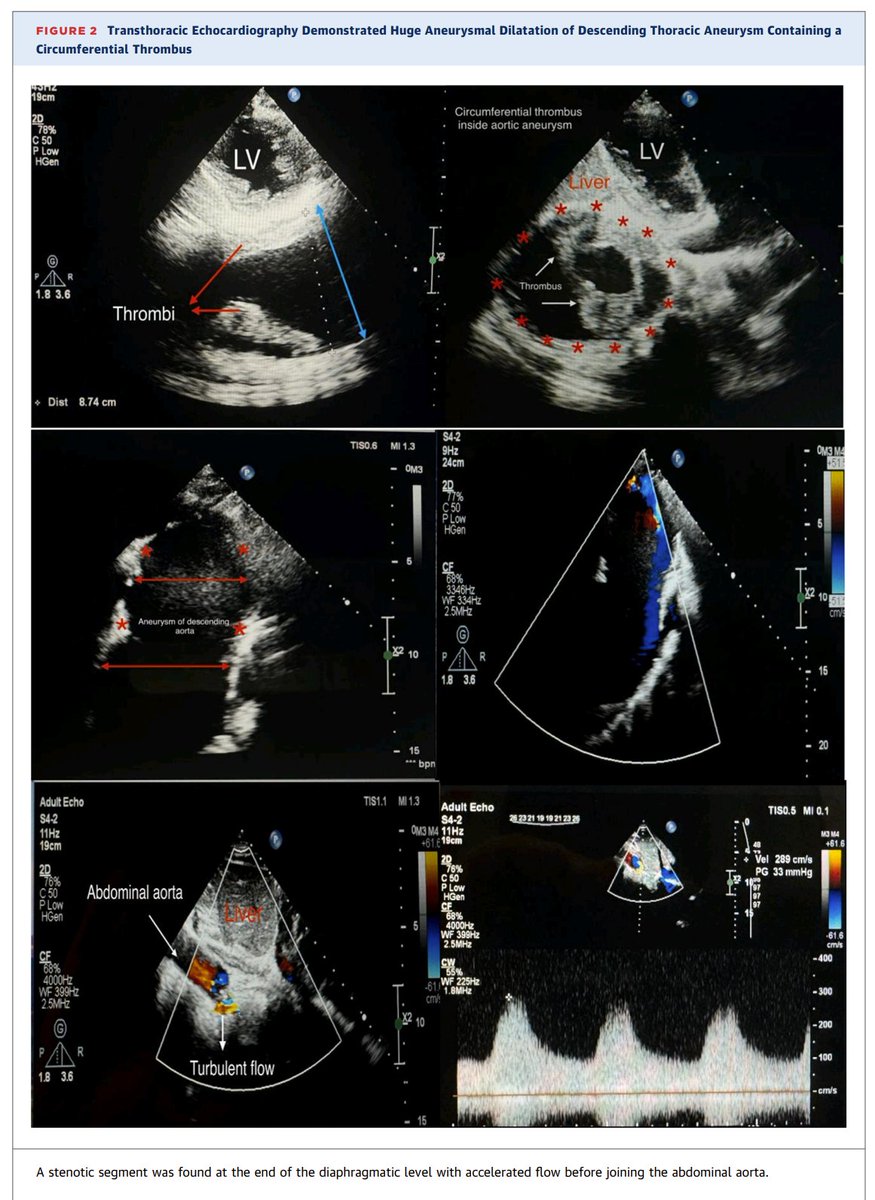

Arterial aneurysms are among the rare vascular manifestations of HIES. We present a case of a 17-year-old girl who had a known history of HIES since childhood. She had a large thoracic descending aortic aneurysm, which required surgical repair to prevent complications

Hyperimmunoglobulin E syndromes (HIES) are a heterogeneous group of primary immunodeficiencies sharing manifestations including recurrent lung infection and significantly raised serum levels of immunoglobulin E.

New publication, JACC case reports A Huge Thoracic Aortic Aneurysm as a Rare Complication of Hyperimmunog... https://t.co/iiAyH7bCaE